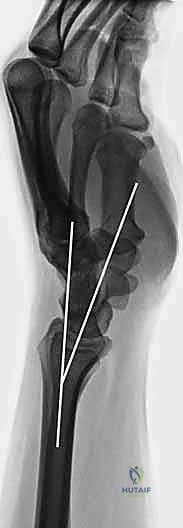

هو المعيار الذهبي الأساسي. يتم أخذ صور من زوايا متعددة (أمامية خلفية، وجانبية) لتحديد:

* موقع الكسر بدقة.

* مدى تفتت العظم.

* مدى انزياح العظم عن مكانه الطبيعي.

* تأثر سطح المفصل (الكسور داخل المفصلية).

3. استخدام جهاز الأشعة المرئية (C-Arm Fluoroscopy)

الخطوة السحرية في هذه العملية هي استخدام جهاز الأشعة السينية الحي (C-Arm). هذا الجهاز يتيح للدكتور هطيف رؤية العظام من الداخل في الوقت الفعلي على شاشة العرض. يتأكد الجراح من أن العظام عادت إلى مكانها المثالي وأن سطح المفصل مستوٍ تماماً.